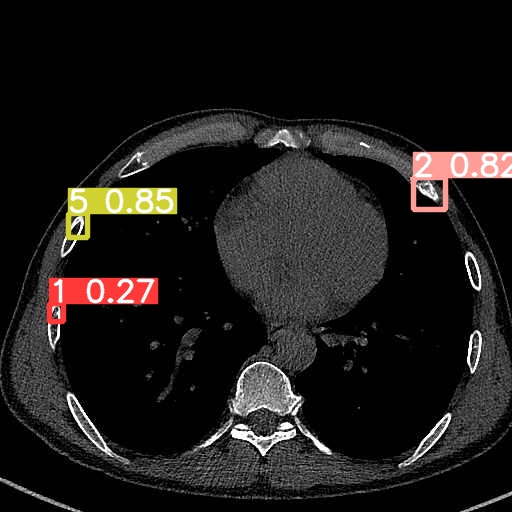

VII-A Experimental Validation of YOLOv9 Model(RQ1)

To validate the reliability of the upstream detection component in our pipeline, we adopt YOLOv9 as the rib-fracture detector and evaluate its performance on the detection task. In this paper, RQ1 reports the detection accuracy of the adopted YOLOv9 module as a prerequisite for providing fracture localization and subtype cues to downstream diagnostic report generation, rather than proposing a new detection algorithm. In our experiments, YOLOv9 achieves a precision (P) of 98.3%, a recall (R) of 89%, and a mean average precision (mAP) at an IoU threshold of 0.5 of 97.2%. These results indicate that the detector can provide effective fracture localization and classification cues for subsequent multimodal report generation.9